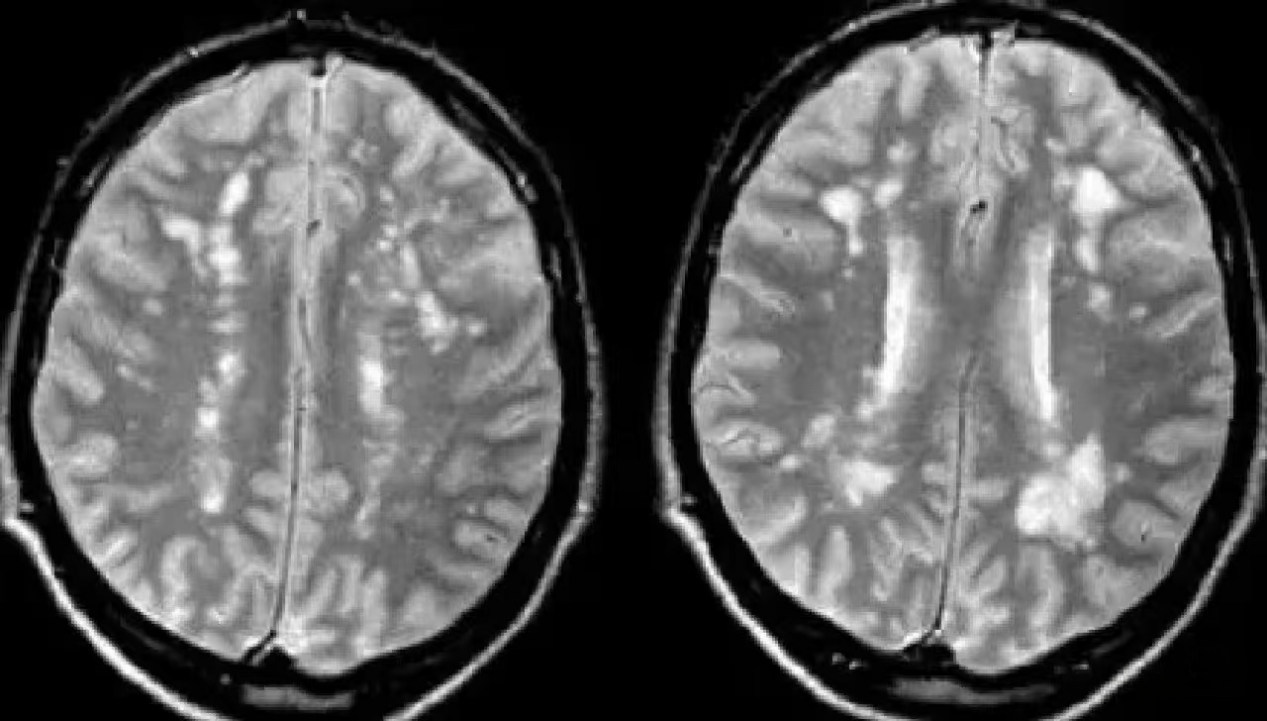

典型表现:病灶数量多、呈椭圆形,且垂直于大脑侧脑室分布(图1),或出现大片融合的异常信号(图2)。

图1